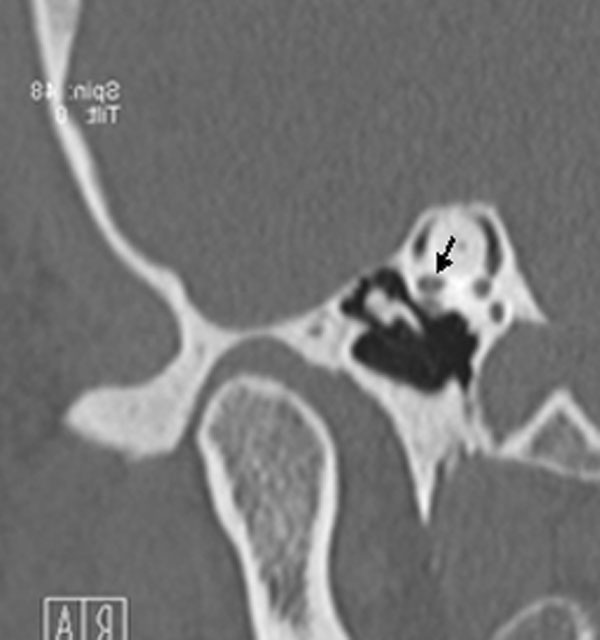

TC de alta resolução. Doente com acufenos não esclarecidos pela clínica. Aquisição reformatada no plano frontal (A) e em Pöschl (B). Em A existe deiscência da espira da cóclea (seta). Em B existe deiscência do canal semicircular superior (seta).